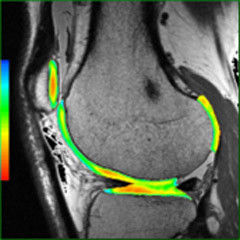

Quantified MR image analysis to enable accurate, confident diagnoses.

READY View helps you get the most from multi-parametric exams by enabling analysis of MR data sets with multiple images for each scan location. The platform offers a combination of protocols, applications, and tools that help you make quantified analyses of multiple data sets quickly and easily.

Provides additional clinical information through time curves and color parametric images.

Enables fusion of color parametric images with anatomical 2D or 3D images with simple "drag and drop" method.

READY View is an image analysis software that allows the user to process dynamic or functional volumetric data and to generate maps that display changes in image intensity over time, echo time, b-value (Diffusion imaging) and frequency (Spectroscopy). The combination of acquired images, reconstructed images, calculated parametric images, tissue segmentation, annotations and measurement performed by the clinician enables a multi-parametric analysis and may provide clinically relevant information for diagnosis.